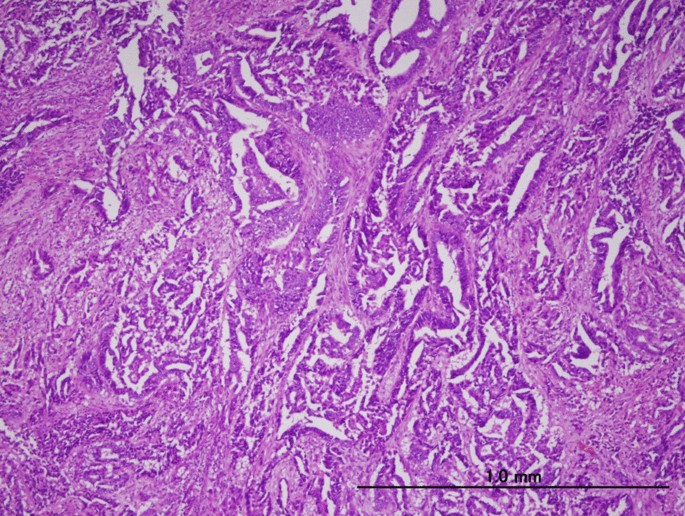

A 72-year-old Japanese woman on medications for hypertension, obesity, and diabetes mellitus, was referred to our hospital with abnormal uterine bleeding. She was previously diagnosed with abnormal endometrial cytology at a previous clinic and visited our hospital for further examination and treatment. Endometrial biopsy revealed an adenocarcinoma (G2), while pelvic magnetic resonance imaging revealed a lesion mass of size 60 × 66 × 53 mm in the right side of the uterus (Fig. 1), which was suspected to invade the serosal side. An enlarged lymph node measuring 18 mm was also found in the lymph node clusters in the right internal iliac artery and the obturator lymph node. Therefore, hysterectomy, bilateral adnexectomy, pelvic lymph node dissection, and para-aortic lymph node dissection were performed. A pathological examination using surgical specimen revealed endometrial serous carcinoma (Fig. 2). Finally, she was diagnosed with stage III C2 endometrial cancer.